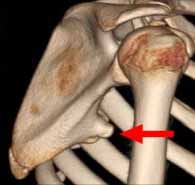

پزشک معالج بعد از معاینه بیمار معمولا از رادیوگرافی ساده برای تایید تشخیص این شکستگی استفاده میکند. بندرت برای بررسی بیشتر محل شکسته شده نیاز به استفاده از سی تی اسکن پیدا میشود.